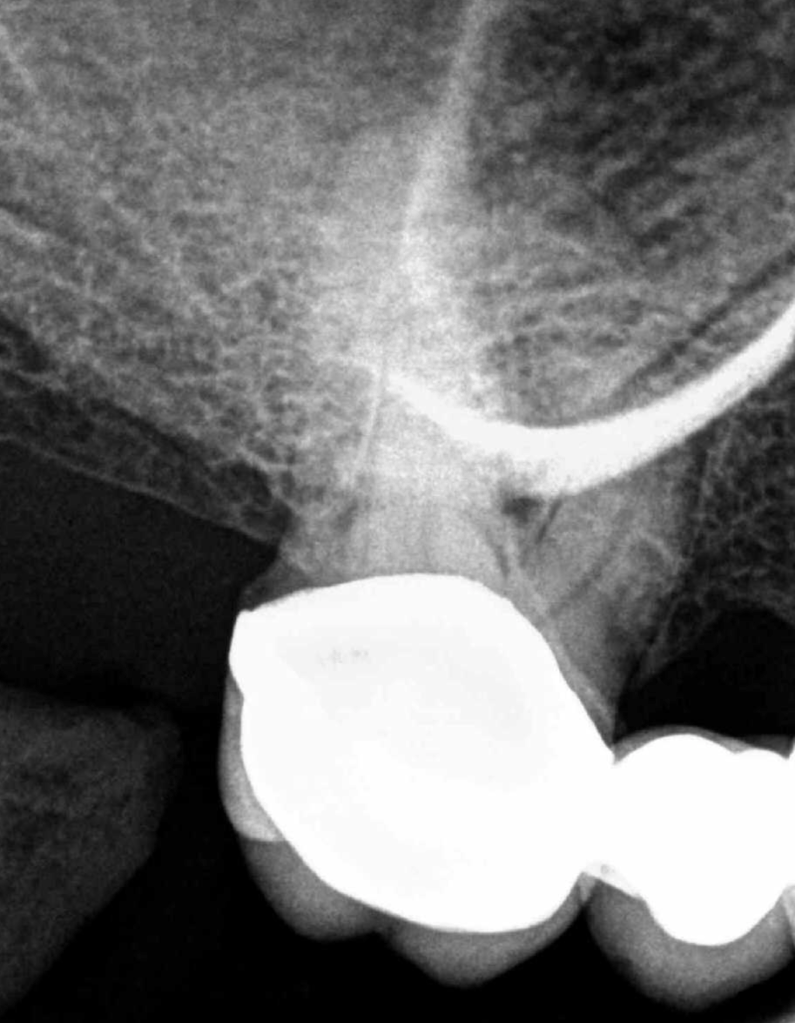

Pulpotomía biodentine + reco preendio